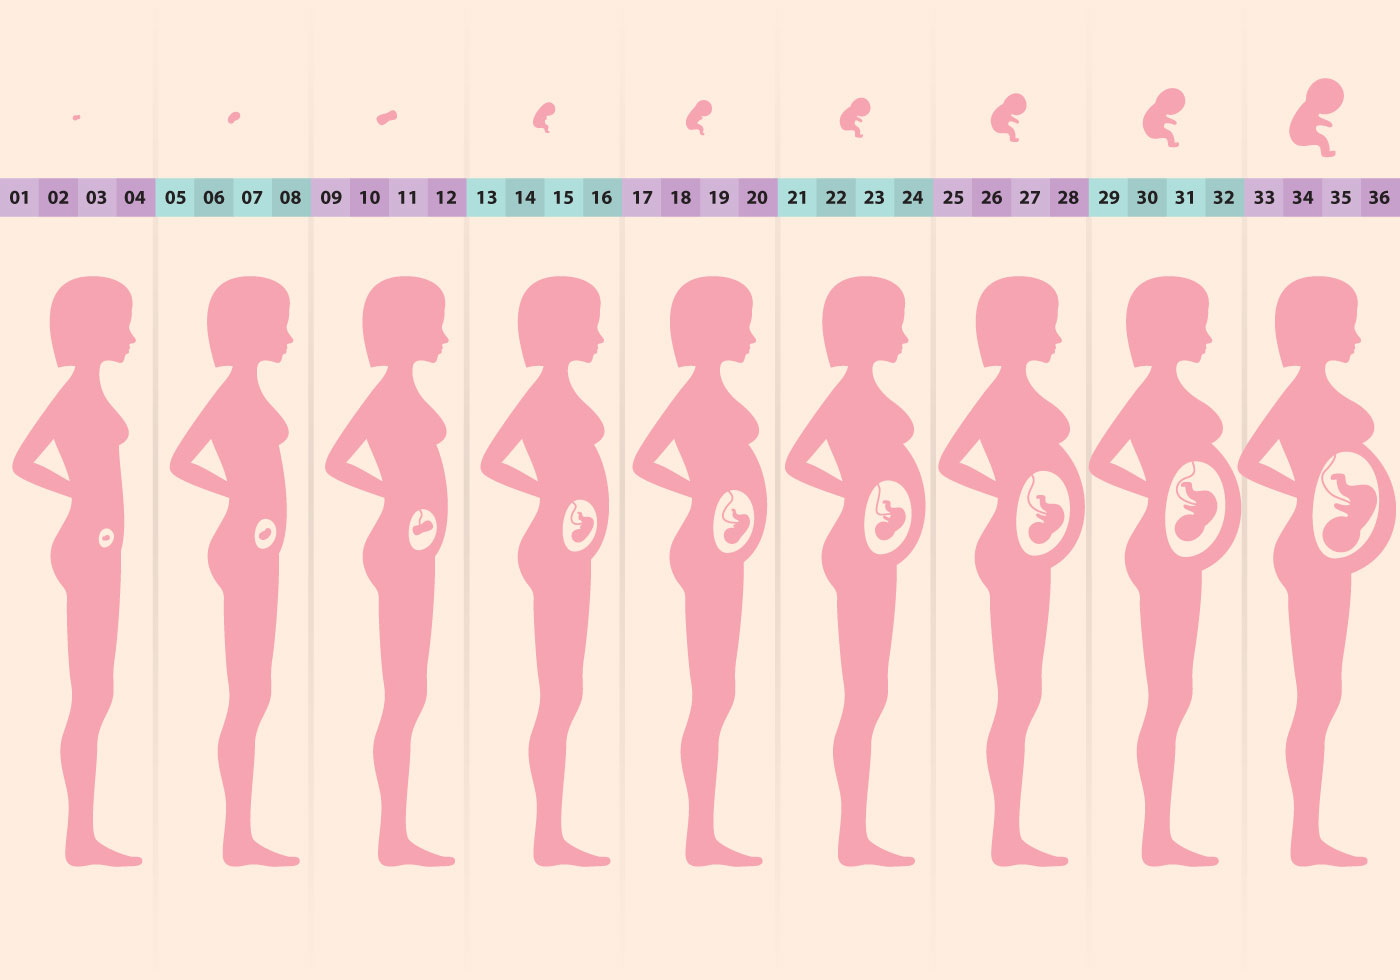

Формирование Плода в Первом Триместре: Важные Этапы